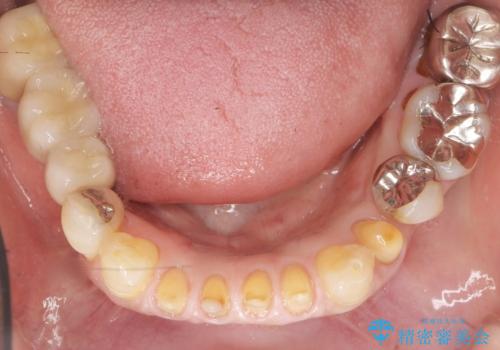

前歯がかけた、ぐらぐらする 60代女性

- 下の前歯が欠けてぐらぐらすることを主訴に来院された患者様です。

以前行った奥歯の治療により下顎前歯の動揺は改善傾向にあり顕著ではなかったのですが、欠けて黒くなっていることと少しの動揺が気になるとのことでした。

元気なうちに治療しておきたいという患者様の強いご希望により、下顎前歯の連結補綴と欠けている小臼歯の補綴治療を行いました。

自然な仕上がりに喜んで下さいました。

クラウンを連結することにより気にされていた動揺もなくなり、安心して頂けました。

被せ物の種類:オールセラミッククラウン スタンダード